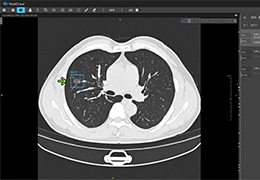

成像智能。

Eclipse 成像智能功能提供强大的处理能力和最佳质量的影像,同时减少质量错误并提高剂量效率。

凭借 AI、专有算法和先进的影像处理能力,提供出色的影像质量和无与伦比的诊断信心。

与标准影像处理相比,智能降噪功能可使客户降低辐射剂量,而不会损失影像质量。这在新生儿和儿科成像中尤其重要,在这种情况下以尽可能低的剂量成像至关重要。

提供相配视图选项,以减少所需的曝光次数,并提供更清晰的感兴趣区域视图。